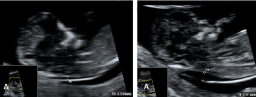

Ecografía de feto de 12 semanas moviéndose

Las imágenes de este bebé de 12 semanas de gestación no dejan lugar a dudas en cuanto a su vitalidad. Se mueve con energía y, lo más curioso, los movimientos los realiza principalmente desde la posición erguida, apoyándose en ocasiones en la pared uterina de su madre. Más que un bebé, da...